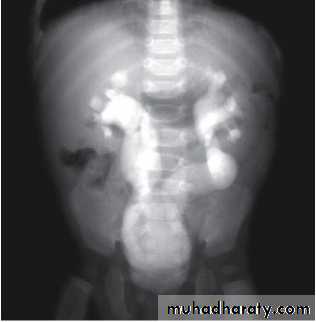

Grading of VUR

The degree of reflux is graded I–V.Grading is based on the appearance of contrast agent in the collecting system during voiding cystourethrography (VCUG(.